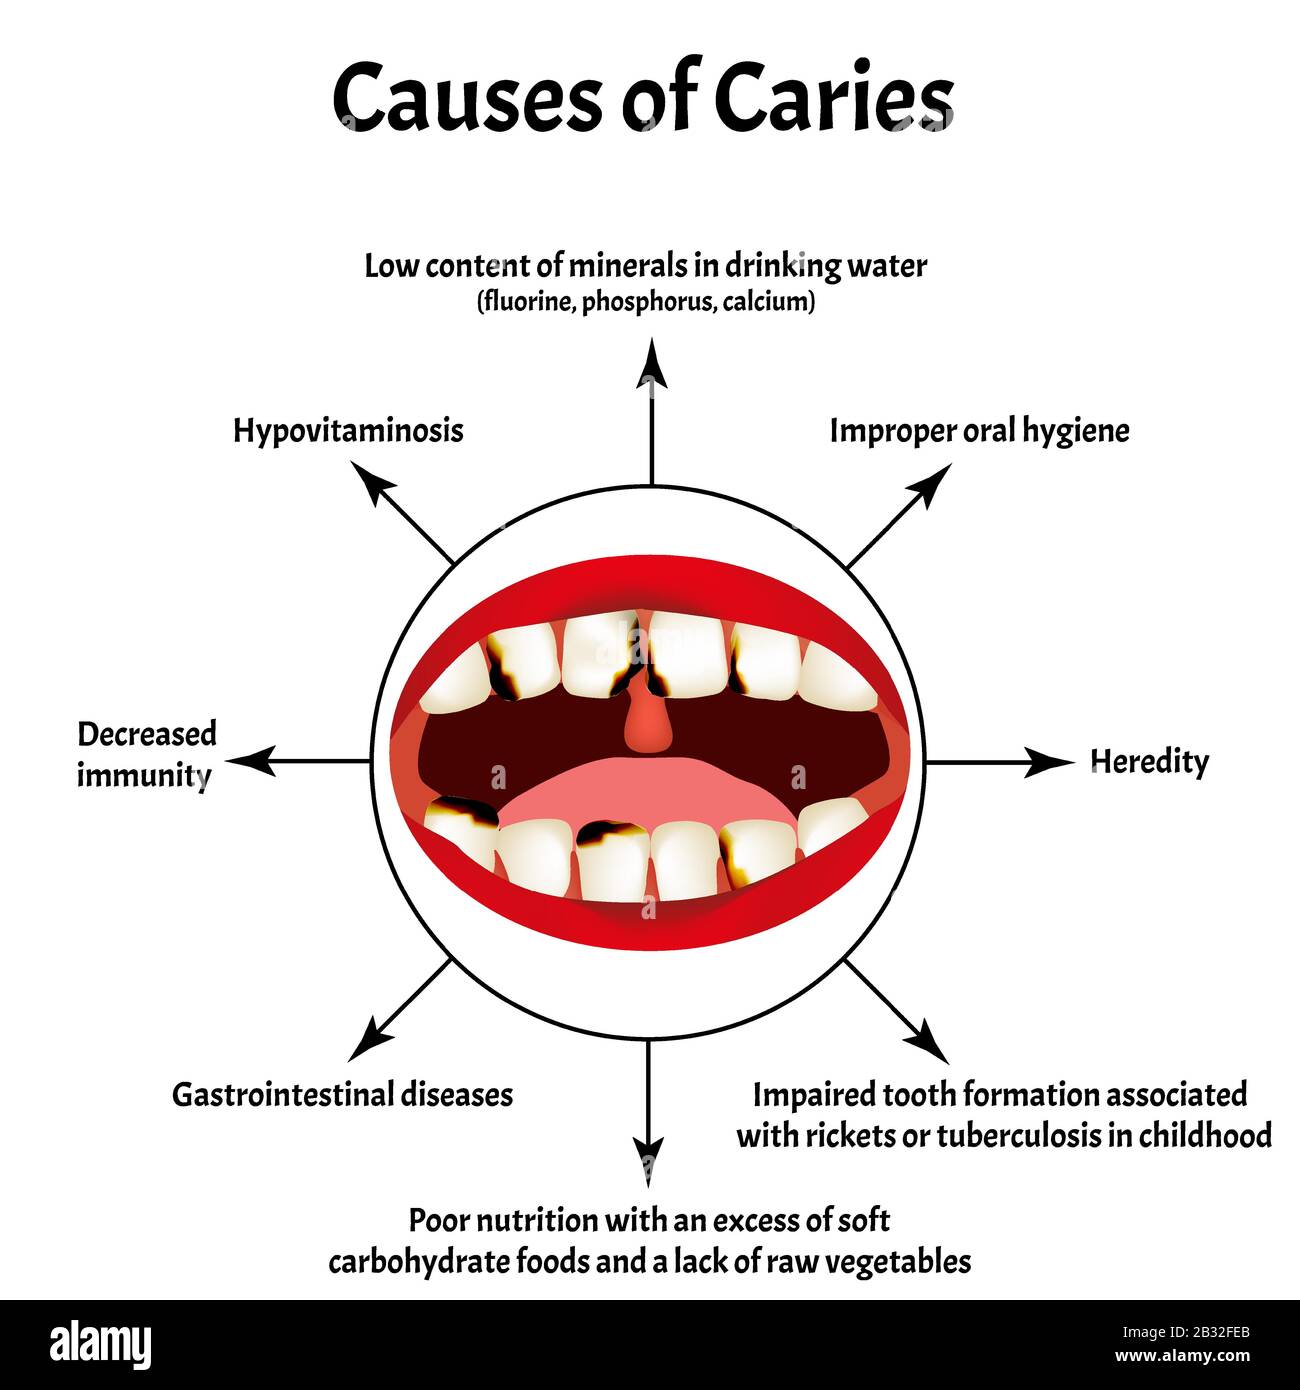

Understanding Dental Caries; Causes, Signs & Symptoms, Prevention

www.theperiodontist.co.ke

www.theperiodontist.co.ke

caries dental causes treatment understanding symptoms prevention signs tooth

Causes And Treatment Of Dental Caries | Blog Now

ahoa.es

ahoa.es